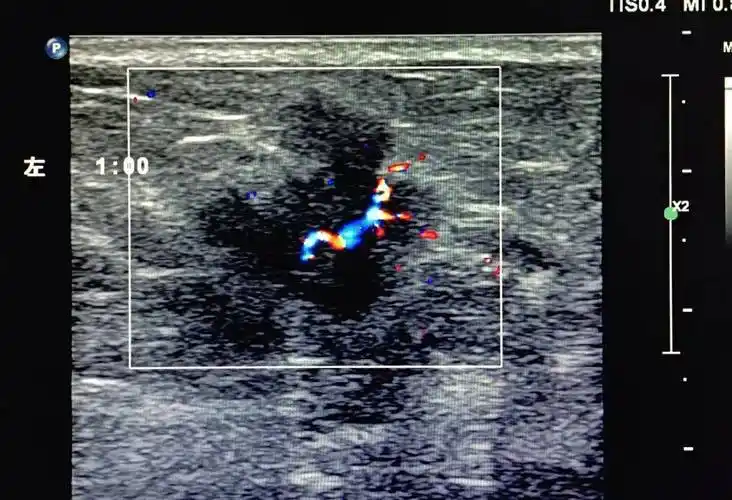

关于乳腺癌你了解多少